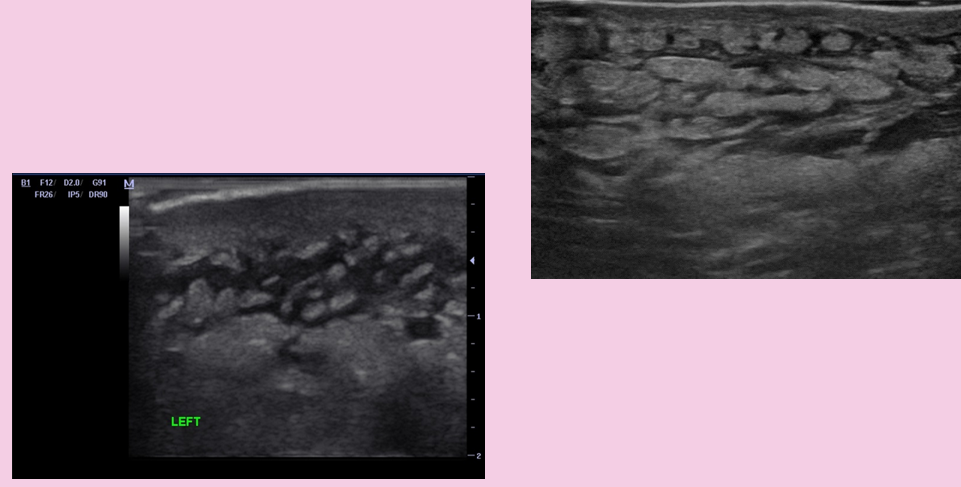

what are the nonvascular pathology findings during venous exams?

hematoma

lymph nodes (usually seen in groin, neck and axillary)

what is this?

can be cystic, solid or complex

enlarged groin lymph node